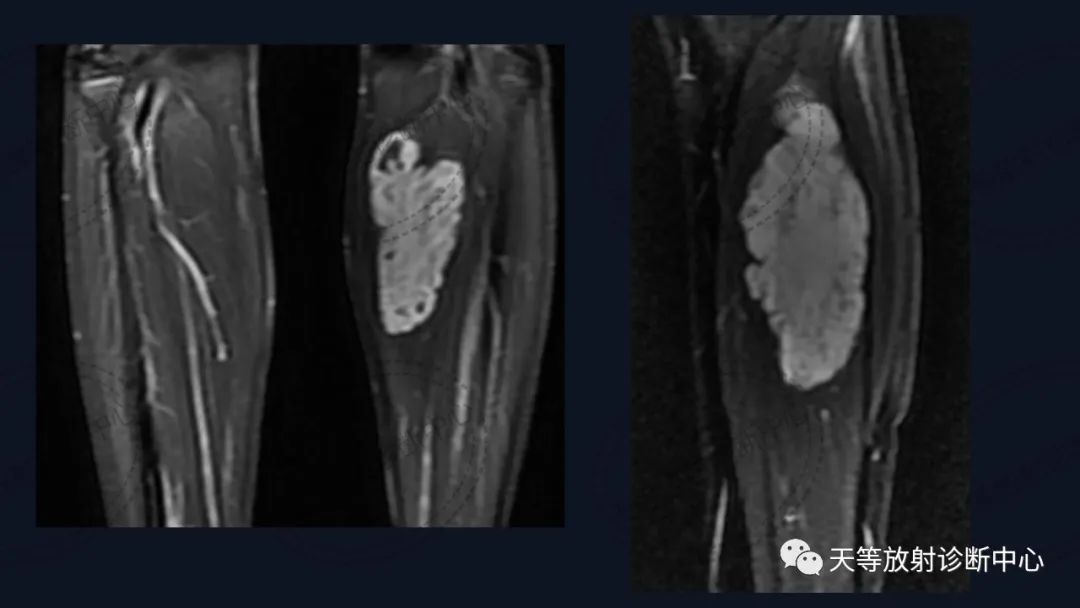

前后两次对比观察,病灶略有增大。

血管瘤

组织学上主要表现为血管管道数目的增加及纤维结缔组织、平滑肌、炎性细胞和毛细血管、淋巴管等不同程度的浸润。MRI观察病灶内纤维结缔组织呈分隔状及线状低信号影,含血管成分可表现血管流空信号影。病灶内出血表现信号混杂等。